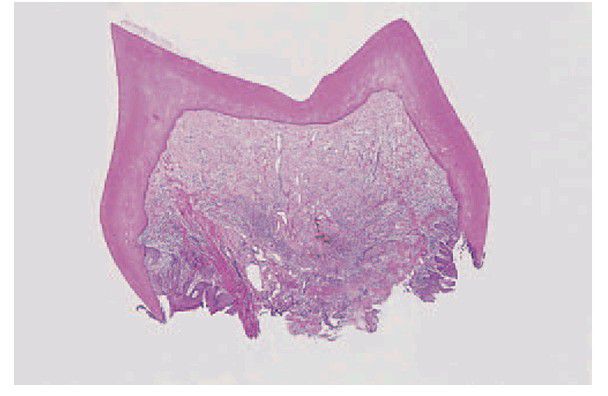

Shell tooth.

In this severe form of dentinogenesis imperfecta, only a thin mantle of dentine is formed and no root develops.